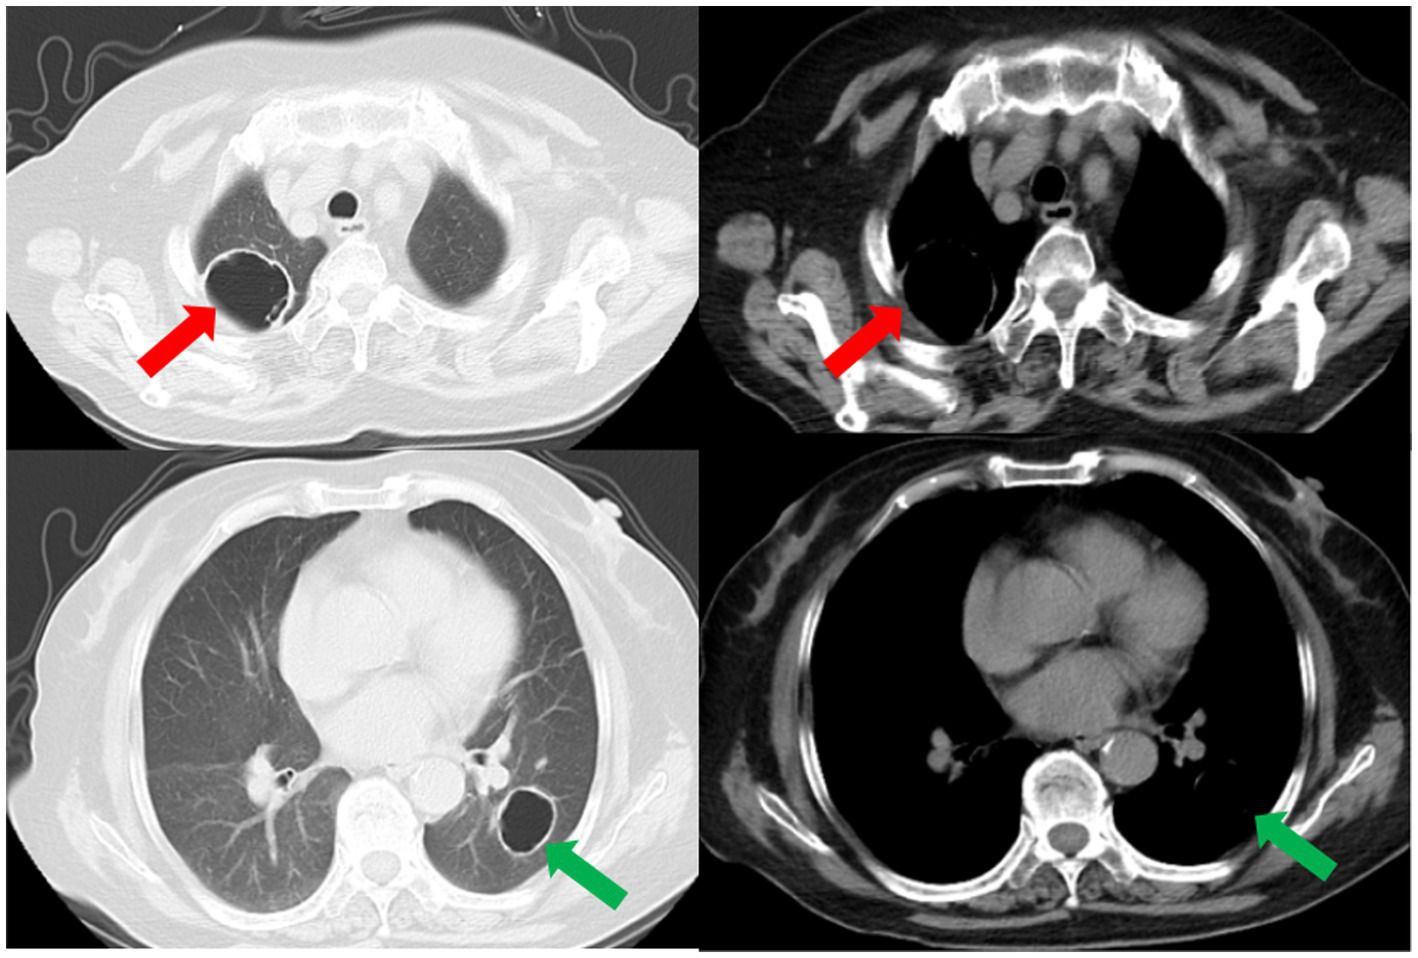

Laboratory results upon admission showed a white blood cell count of 14.29 × 109 cells/L (reference range: 3.5–9.5 × 109 cells/L) with an elevated neutrophil ratio of 88%. C-reactive protein and procalcitonin concentrations were markedly elevated at 81.40 mg/L (0–3.48 mg/L) and 1.20 ng/mL (0–0.05 ng/mL), respectively. Serum 1-3-beta-D-glucan and galactomannan tests yielded negative results. CT scans of the patient’s lungs on admission revealed multiple lung nodules and patchy infiltrations (Figure 1). The sequence of relevant events after the patient was admitted has been shown in the timeline (Figure 2).

Figure 1

www.frontiersin.org

Figure 1. CT scans of the thorax on the day of admission demonstrates multiple nodular and patchy infiltrates in the lungs. Nodular infiltrate in the right lung (red arrows). Nodular infiltrate in the left lung (green arrows). Patchy infiltrates in both lungs (blue arrows).